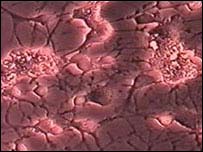

Neurônios

O cérebro continua a produzir neurônios depois de adulto

Durante o processo, eles fotografaram imagens das células a cada cinco minutos usando um microscópio especial.

Com as fotos, os cientistas criaram um "curta-metragem" mostrando o desenvolvimento das células passo a passo, até elas se tornarem neurônios.